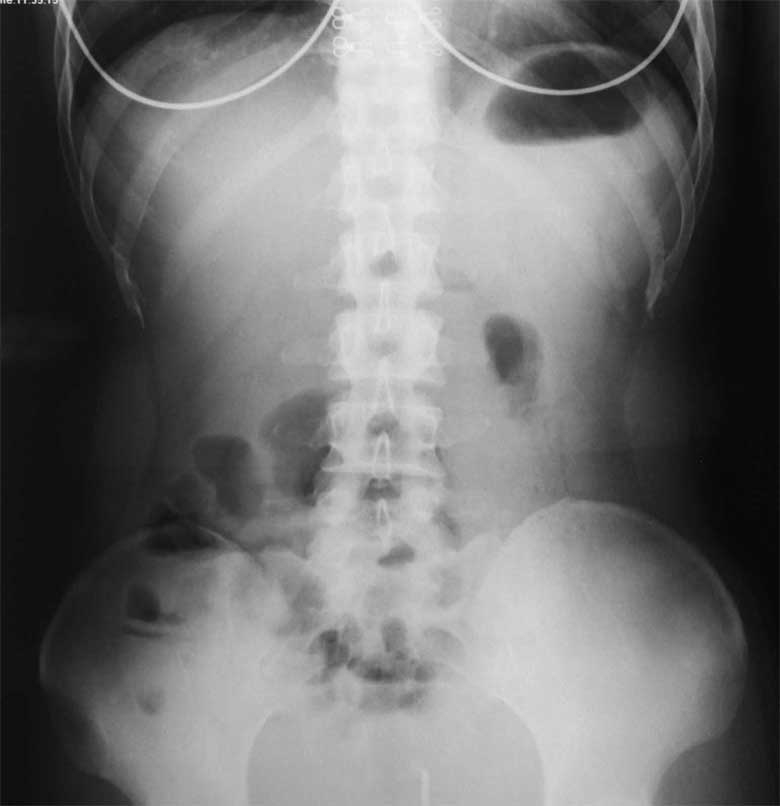

1.病变的分布 本病从口至肛门的全胃肠道的任何部位均可受累,病变呈跳跃式或节段性分布。小肠和结肠同时受累最为常见,占40%~60%;限于小肠,主要是末端回肠发病的占30%~40%;单独发生在肛门或直肠的病变少见,约占3%,多与小肠和结肠病变合并存在;结肠单独发病者较少,占5%~20%。胃或十二指肠、食管、口部病变总共约占10%以下。